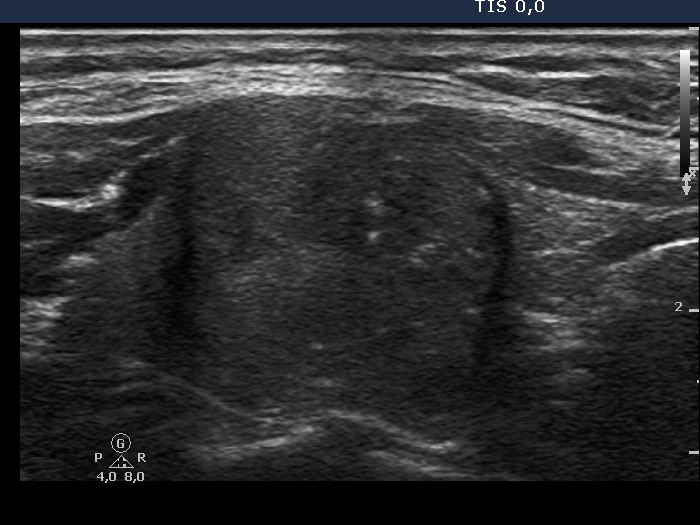

Intranodular hyperechogenic figures - case 401 (ultrasonographic picture 6)

Left lobe, longitudinal scan. The borders of the nodule are irregular.